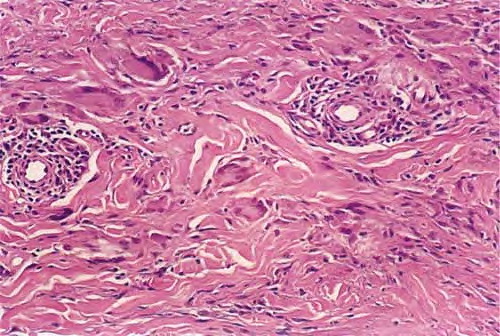

Graft versus Host Disease =داء رفض الطعم للمضيف Graft Versus Host Disease GVHD occurs in situations in which donor immunocompetent T cells transferred into allogenic hosts are incapable of rejecting them. The sources of the T cells include primarily peripheral blood stem cell and bone marrow transplants and, infrequently, unirradiated blood products , solid organ […]